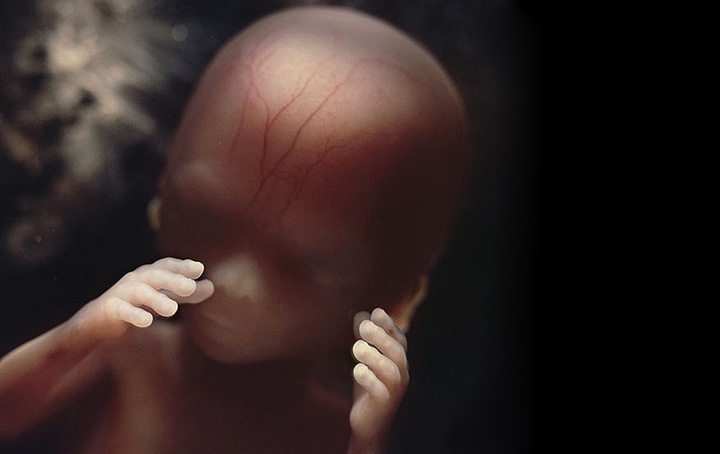

Как выглядит ребенок

Кроха растет, его тело приобретает пропорции, скелет укрепляется. Малыш размером с большую луковицу или небольшой грейпфрут, вес колеблется от 130 до 230 г. Кожные покровы уплотняются, но сосуды все еще видны. На пальцах появляются уникальные отпечатки.

При УЗИ можно рассмотреть черты лица, что радует женщин и усиливает материнский инстинкт. Плод улавливает звуки и речь матери, что свидетельствует о развитии слуха. Специалисты рекомендуют напевать мелодии, чтобы успокоить малыша.